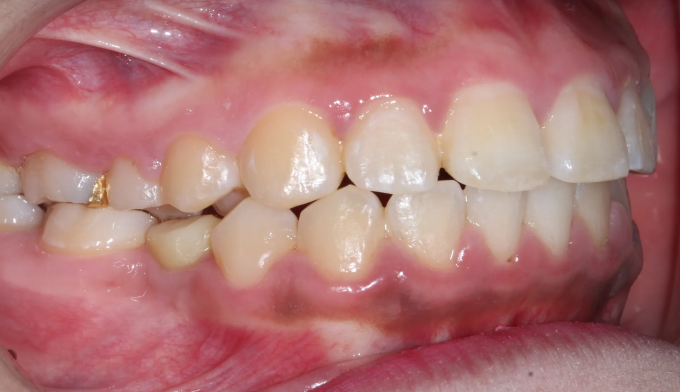

돌출입과 불규칙한 앞니를 가지고 있습니다. 그리고 아래쪽에 ‘임플란트’가 있습니다.

임플란트는 뼈와 강력히 결합되어 있기 때문에 교정치료로 절대 움직일 수 없습니다. 따라서 해당 부위는 절대 교정치료로 움직일 수 없다는 제한점이 있는 상태에서 교정치료를 진행하게 되었습니다.

후방이동이 불가하므로 악궁확장을 통하여 공간확보를 시도하였고, 동시에 돌출감도 해소되었습니다.

최종적으로 임플란트의 존재때문에 중심선을 맞추지는 못했으나 환자분은 너무 만족해하셨습니다.

총 치료기간은 14개월 소요되었습니다.